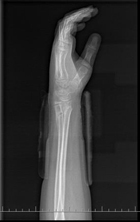

整复后

整复后X线片提示接近解剖复位,40天达到临床愈合,最后随访时患肢外形及功能均完全正常。

闭合整复小夹板外固定后,即刻复查X线片见桡尺骨骨折对位对线优良,指导患者握拳活动。